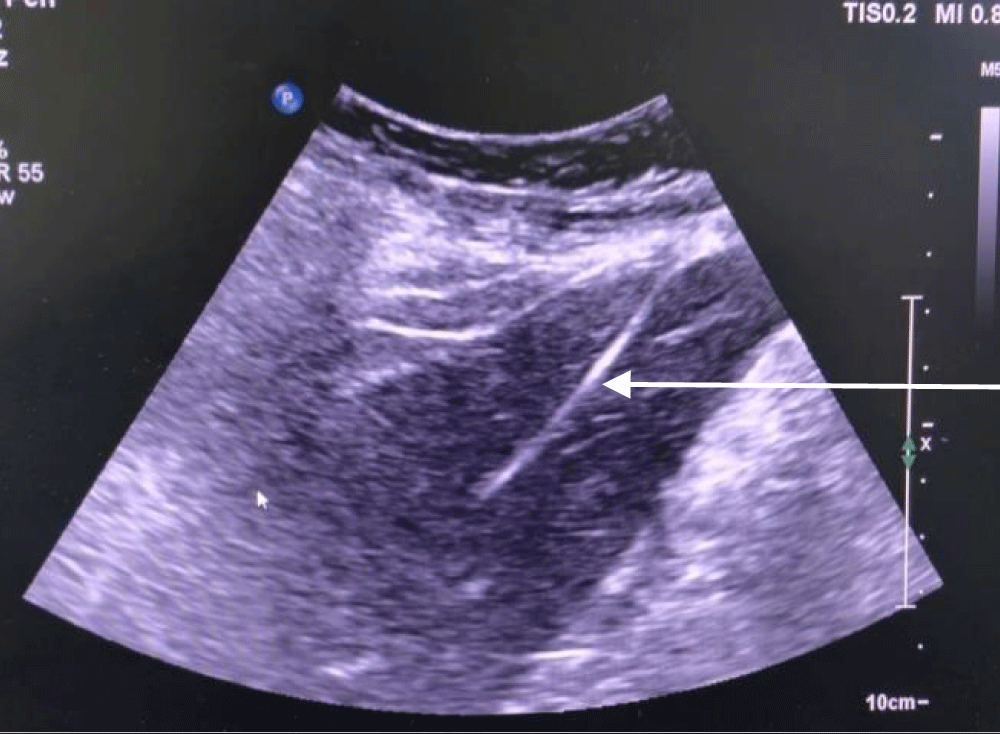

The patient was taken to the cath lab where the procedure was done under ultrasound and fluoroscopy guidance. The procedure was done with a sterile technique and using anti-septic measures; in the cath lab. After cleaning and draping the abdomen, first the right hepatic vein was visualized via ultrasound, and it was punctured by a Chiba needle via the percutaneous route. A guide wire was passed and its position was traced by ultrasound (Figure 1) and fluoroscopy (Figure 2). Radial artery sheath and Kumpe catheter were used as needed to negotiate guide wire in the inferior vena cava and right atrium. A subcutaneous tunnel of 5 cm was created and a tunnelled dialysis catheter was pulled through it (Figure 3). Contrast was injected into the sheath to visualize its flow. The contrast was seen flowing in the right atrium confirming the correct position of the sheath and the kumpe wire (Figure 4). The guide wire was then reinserted into the sheath. As the guide wire reached the inferior vena cava, it was negotiated to the right atrium. This was followed by the removal of the sheath and kumpe wire. After confirming the position of the guide wire in the right atrium (Figure 2), sequential dialation of the tract was done by dilators 6 fr, 8 fr, 10 fr, 12 fr, 14 fr, and finally 14.5 Fr x 19 cm trans-hepatic tunneled dialysis catheter was secured along with subcutaneous tunnel (Figures 5,6). The catheter tip was kept at the junction of the right atria – inferior vena cava (Figure 5). Ultrasound of the liver was done to rule out haemorrhage. There was slight post-operative pain post catheter insertion which subsided after a while. She was kept in the intensive care unit for a day for monitoring of vitals and was moved to the ward the next day. The procedure was uneventful. After being discharged, the patient underwent multiple sessions of hemodialysis with this access. She was told to take proper hygiene care of the area where the catheter was inserted to prevent catheter-related bloodstream infections. She once had an upper respiratory tract infection following which she had poor flow from the tunneled trans-hepatic dialysis catheter. She underwent repositioning of the catheter in the cath lab following which good flow was achieved. She was explained to avoid forceful coughing which can displace the catheter from its position; hampering the flow.

Figure 1: Guide wire (arrow pointing at it) traced via ultrasound in the inferior vena– cava after puncturing the right hepatic vein by Chiba needle and inserting the guide wire.